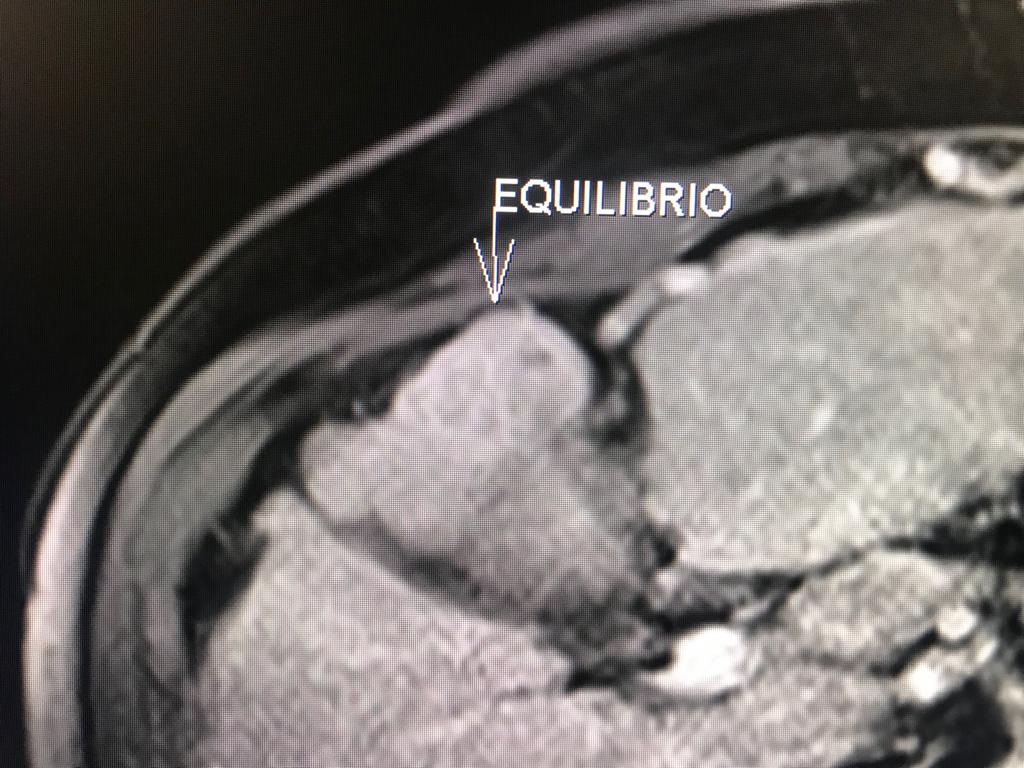

En el presente caso, encontramos una lesión típica de hepatocarcinoma en el segmento 5 ( hiperintensa en T2, restringe en la Difusión con ADC bajo. Realza heterogéneamente postcontraste EV, con wash out y presencia cápsula tardía).

El objetivo es identificar dentro de la multifocalidad de nódulos , un hepatocarcinoma precoz o de pequeño tamaño , cuando la posibilidad de tratamiento con intención curativa es viable , a pesar de la cirrosis.